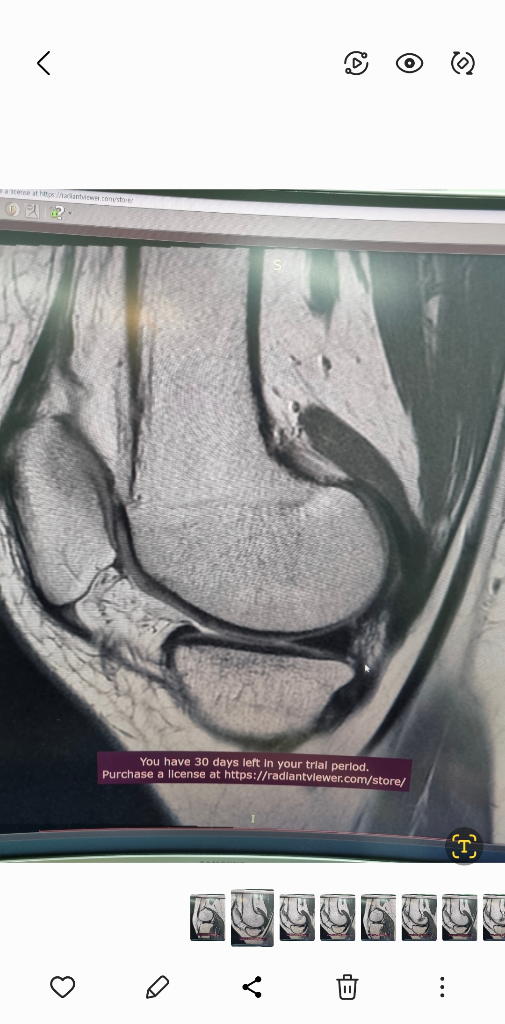

1. 추벽이 아닙니다.

2. 슬개골 관절면에 외상으로 인한 골수부종입니다.

3. 관절면 손상여부는 첨부해주신 영상만으로 알 수 없습니다